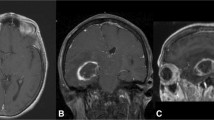

Example of a poorly centered craniotomy using neuronavigation in a supine case. (A-C) Preoperatively, T1 MRI was performed with and without gadolinium contrast agent at 1 mm resolution. The axial (a), sagittal (B), and coronal (C) images demonstrate a superficial, spherical mass measuring 19 mm × 15 mm × 20 mm in the right frontal lobe, consistent with a metastasis. (D–G) Intraoperatively, the craniotomy borders were planned on the exposed skull using neuronavigation to center the tumor. After craniotomy (black, solid line), white light imaging (D) does not visualize the tumor. However, based on white light imaging during and after resection, the tumor boundary was transposed onto the dura (white, solid line) and the tumor center is shown (black triangle). With near-infrared fluorescence imaging (E), the fluorescence from the tumor is clearly visible (black, dotted line) and the NIR center (black, dotted circle) closely approximates the tumor center (1.9 %). The neuronavigation center (black square), in contrast, aligns poorly with the tumor center, with 27.1 % deviation. The tumor is visible with white light after durotomy (F), and the location of near-infrared fluorescence is confirmed to be coming from the tumor (G). Prior to durotomy, the surgeon felt more confident in the fluorescence imaging results than in the neuronavigation, so durotomy was performed over the site of fluorescence rather than over the neuronavigation center.

Transdural Neuronavigation of Gross Tumor

The Stryker neuronavigation system was used in 21 cases, followed by BrainLab (n = 17), BrainLab Curve (n = 14), and Medtronic Stealth (n = 4). Senior neurosurgery residents (postgraduate year 4 or greater) performed 44/56 registrations, while junior residents performed 12/56. In order to assess neuronavigation reliability in this retrospective study, the accuracy of craniotomy placement was used as a surrogate. Compared to the tumor center, the Neuronavigation Center was, on average, 23.0 ± 7.7 % (range 4.3–47.6 %) deviated relative to the size of the craniotomy. Deviations < 15 % (Fig. 1) were not largely noticeable intraoperatively; conversely, deviations > 15 % (Fig. 2) were easily recognized as such. In 12 cases of severe neuronavigation inaccuracies, dura opening was significantly altered based on NIR fluorescence.